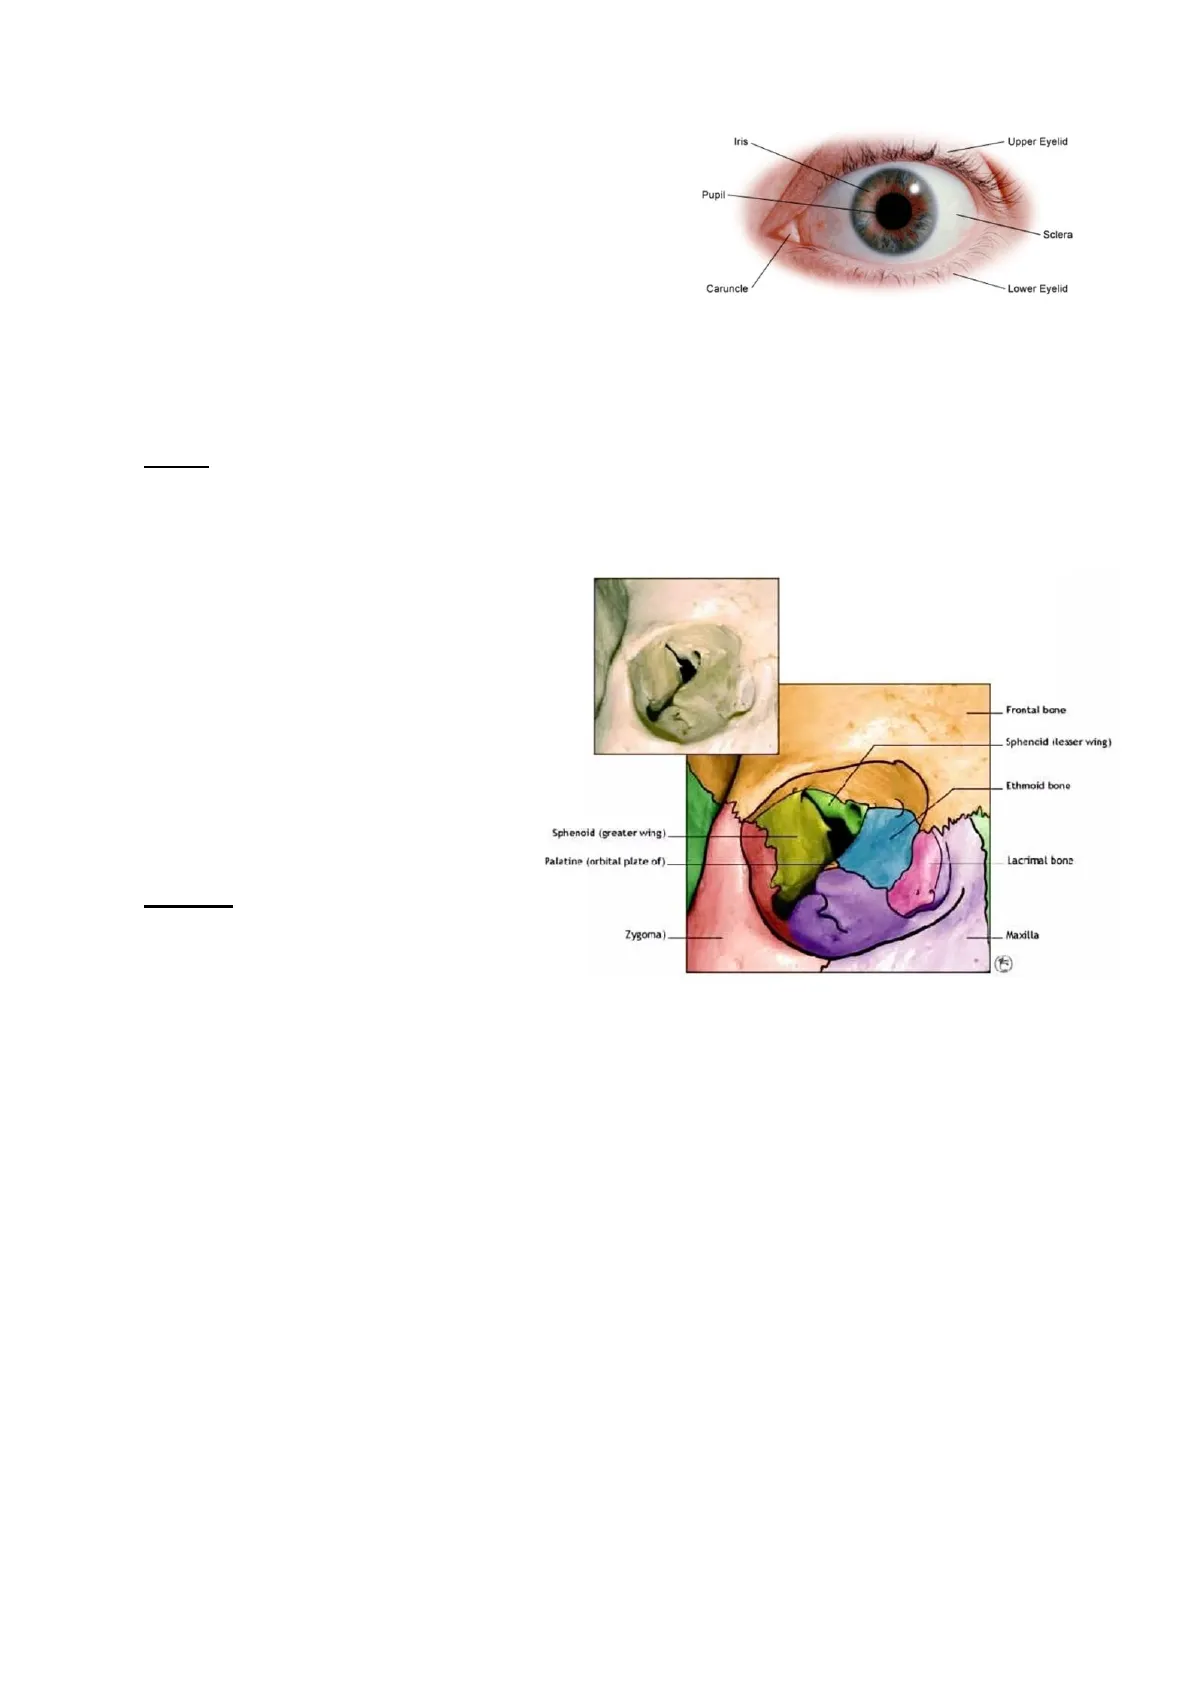

Iris Upper Eyelid Pupil- Sclera Caruncle Lower Eyelid

Osserviamo le ossa che compongono l'orbita:

Frontal bone Sphencid ilesser wing) Ethmoid bone Sphenoid (greater wing) Palatine (orbital plate of) Lacrimal bone Zygoma) Maxilla